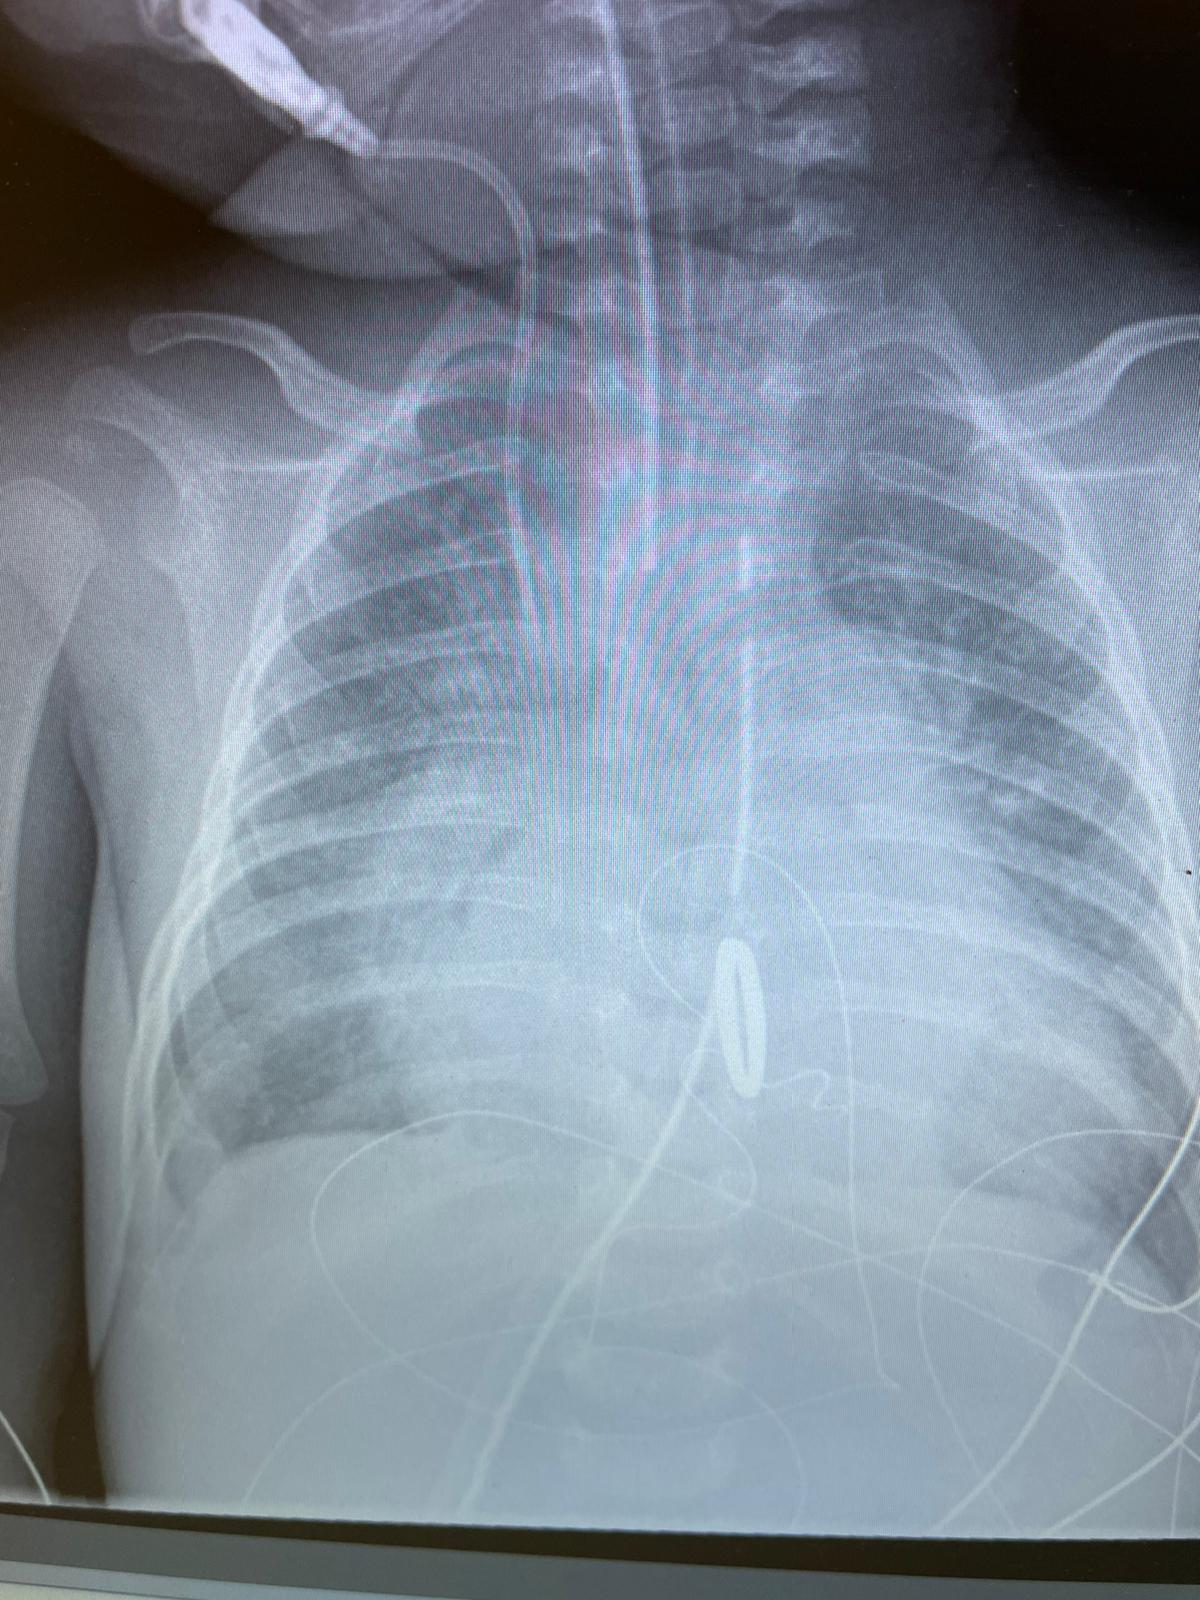

Użyto najmniejszej, dostępnej od niedawna, zastawki Abott’s Masters (St. Jude) HP 15 mm specjalnie sprowadzonej na potrzeby operacji. W dniu zabiegu dziecko ważyło 3,8 kg. Operacje wymiany zastawki mitralnej u pacjentów poniżej 1 roku życia należą do niezwykłej rzadkości, a w przypadku masy pacjenta poniżej 4 kg można śmiało mówić o wydarzeniu.

Operacja przebiegła bez powikłań, a funkcja serca z każdym dniem ulegała poprawie. Od kilku dni niemowlę przebywa już w Klinice Kardiochirurgii i Chirurgii Dziecięcej DSK UCK WUM, w stanie ogólnym dobrym, na oddechu własnym.